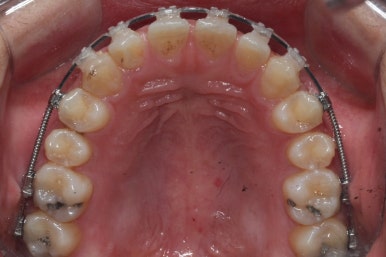

다음 단계는 작은 어금니 부위에 모아진 틈을 없애는 것입니다. 앞서도 말씀을 드렸듯이 앞니의 앞-두로의 위치는 변화 시키면 안되기 때문에 오로지 어금니를 앞으로 당겨오면서 틈을 모아줘야 합니다.

바로 미니스크류 입니다. 위 사진에서 화살표 부분이 바로 미니스크류 입니다.

뼈에 단단히 고정해 놓고 어금니를 앞으로 당겨오는데 사용을 하게 됩니다. 교정치료 후에는 제거하게 되며 긍방 뼈가 차기 때문에 별로 걱정은 하지 않으셔도 됩니다.

서서히 틈이 줄어들고 있는 것이 보입니다.

벌써 몇 군데는 틈이 다 모였습니다.

이제 거의 다 끝나가고 조금 더 마무리하면 됩니다.